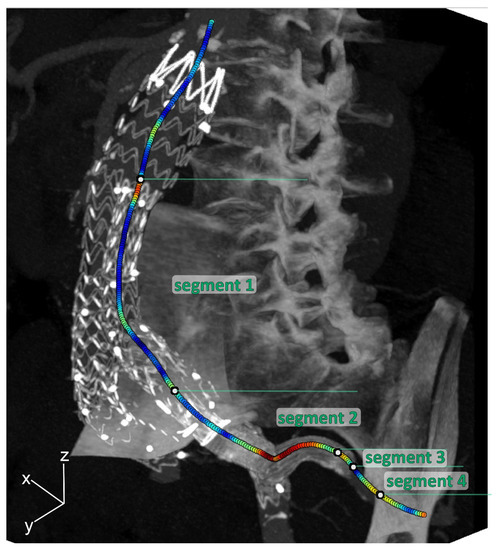

To quantify geometrical parameters, centerlines from the aorta to the IIA were obtained in Aquarius Intuition (version 18, TeraRecon, Inc., Foster City, CA, USA) on the static CT volume. By means of backward mapping using the deformation fields, the centerline of the static CT volume was converted to the centerlines of the individual phases. The centerlines were divided into the following 4 segments for further analysis (see Figure 2):

• Segment 1: main EVAR flow divider—IBD flow divider;

• Segment 2: IBD bifurcation—5 mm upstream of the end of the IIA component;

• Segment 3: 5 mm upstream of the end of the IIA component—5 mm downstream of the end of the IIA component;

• Segment 4: 5 mm downstream of the end of the IIA component—first native IIA bifurcation.

Figure 2. Three-dimensional maximal intensity projection of the mid-cardiac cycle volume example, including curvature color-coded centerlines (red is high curvature; blue is low curvature) for the internal iliac artery (IIA), which was divided into 4 segments: Segment 1: main EVAR flow divider—IBD flow divider; Segment 2: IBD bifurcation—5 mm upstream of the end of the IIA component; Segment 3: 5 mm upstream of the end of the IIA component—5 mm downstream of the end of the IIA component; Segment 4: 5 mm downstream of the end of the IIA component—first native IIA bifurcation.